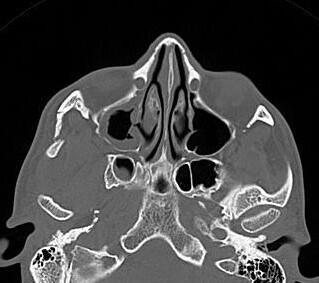

Ammar Haouimi, Radiopaedia.org. From the case rID: 184892